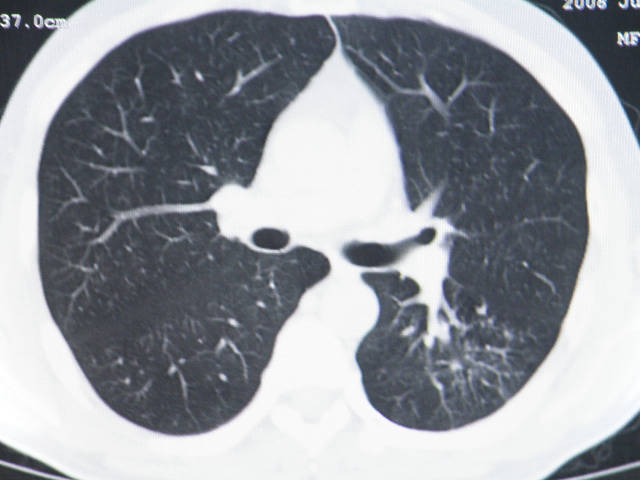

肺内结节在纵隔窗内测ct值为43hu

来源于肝脏mt伴淋巴结肿大,肺内病灶无纵隔窗,mt首先考虑.

左肺下叶背段软组织结节,偏心空洞,周围见长纤维所条及卫星灶,首先考虑结核球,周围型肺癌待排。

左肺下叶偏心软组织肿块,边缘毛刺征,胸膜凹陷征

手术效果不会太好,腹腔病变考虑恶性间质瘤,肺内结节肺癌可能性大,(楼主未提供纵隔窗,结核不能除外)最好术前明确诊断.

有肝硬化背景,肝胃间隙见不规则形,且密度不均匀的占位性病变,与肝左叶分界不清,首先考虑外生性肝癌可能性大,不排外肝胃间隙恶性占位肝脏受侵可能性。左肺下叶结节影,其内见空泡征,边缘见毛刺,从一元化的角度首先考虑转移。

1 肝脏各叶比例失调,形态失常,外缘呈波浪状。右叶萎缩,左叶 尾叶增大。2 腹腔内软组织密度肿块,低于肝实质密度,内见低密度区,并与肝脏界限欠清。腹膜后见肿大淋巴结,并与腹腔肿块关系密切。3 左肺下叶肿块,见边缘毛刺征及胸膜凹陷征,并与近肺门侧见异常血管相连。

综合考虑:左下肺周围性肺癌伴腹腔 腹膜后淋巴结转移!另:肝硬化!

左肺下叶偏心软组织肿块,边缘毛刺征,胸膜凹陷征,血管集束症

1肝胃韧带区域一肿块,肿块上缘与肝左叶相连。肝硬化。考虑肝外生型肝癌可能性大,不除外间质瘤。2左肺下叶背段一结节,有偏心性空洞,长毛刺,其周有多发小结节。考虑结核可能性大。

,腹腔病变考虑恶性间质瘤,肺内结节肺癌可能性大,(楼主未提供纵隔窗,结核不能除外)最好术前明确诊断.

一元论:肝硬化、外生性肝癌并左肺转移;但不除外左肺周围型肺癌可能。

那肺内病灶如何处理?

肝脏考虑外生型肝癌、肺内考虑结核,应该增强扫描